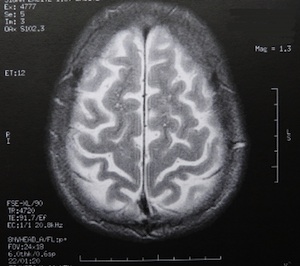

Sie sind hier: Startseite Berichte Wissenschaft Hirnforscher Prof. Dr. Dr. Gerald Hüther: "Die Scheu des Hirns vorm Nachdenken" Bild: pixelio.de/Dieter Schütz